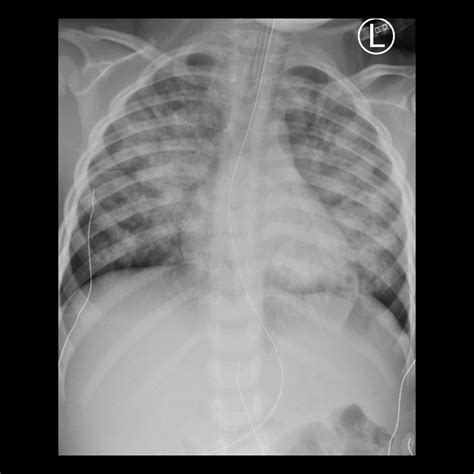

• Bat-wing Opacities: In more severe cases, bilateral central alveolar opacities sparing the periphery of the lungs, indicating profound alveolar flooding.

Differentiating Cardiogenic from Non-Cardiogenic Edema

While the Pulmonary Edema Cxr is excellent at confirming the presence of fluid, determining the etiology is equally important. Cardiogenic pulmonary edema is typically associated with a widened cardiothoracic ratio (cardiomegaly) and vascular redistribution. In contrast, non-cardiogenic pulmonary edema, often seen in Acute Respiratory Distress Syndrome (ARDS), usually presents with a normal heart size, patchy or peripheral infiltrates, and an absence of pleural effusions.

Clinicians utilize the X-ray in conjunction with lab tests like Brain Natriuretic Peptide (BNP) to make a definitive diagnosis. If the heart shadow is enlarged, it strongly suggests a cardiac origin, whereas a normal-sized heart with widespread bilateral infiltrates warrants an investigation into sepsis, transfusion-related lung injury, or other non-cardiac triggers.